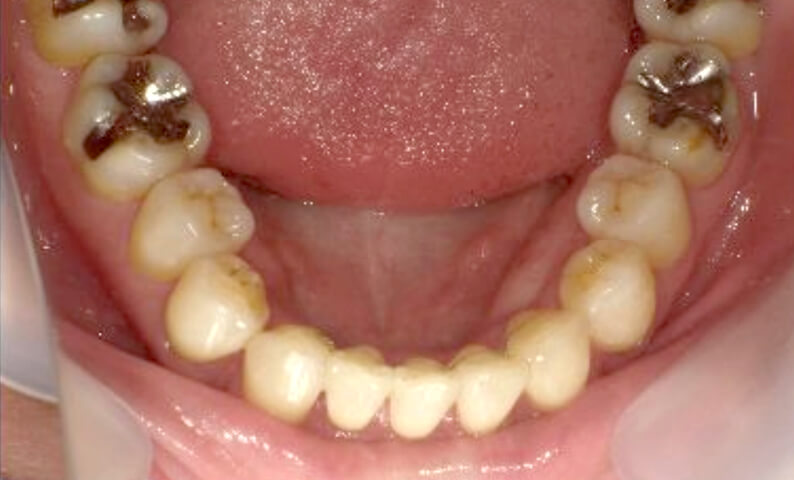

症例_003 下顎だけの部分矯正

治療期間:10ヶ月金額:24万円+税女性前歯のガタガタ下の前歯だけ上顎は補綴治療中

| Before | After |

|---|---|

|